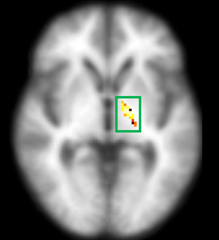

수면무호흡증에 따른 뇌구조 변화

| ▲발생군 |

호전군에서는 시각기억 경로의 회복(노란색)을 확인했으며, 발생군과 지속군에서는 시각기억 관련된 부위의 뇌손상(파란색을) 확인할 수 있다.